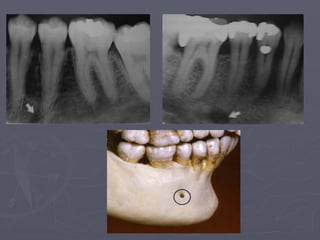

Genial Tubercles

► Also called mental spine.

► Divided right and left,

superior and inferior

promineneces.

► Appears on occlusal

radiographs.

► On peripaical radiographs

it appears as round

radiopacity surrounding

the lingual foramen.

Lingual foramen : radiolucent ‘hole ’ in centre of genial tubercles.

Lingual nutrient vessels pass through this foramen .

Genial tubercles: They appear as radio Opaque circle that

surrounds the lingual foramen just below the apices of the Of

the incisors.

Genial Tubercles ► Alsocalled mental spine. ► Divided right and left, superior and inferior promineneces. ► Appears on occlusal radiographs. ► On peripaical radiographs it appears as round radiopacity surrounding the lingual foramen.

• 37.

Lingual foramen :radiolucent ‘hole ’ in centre of genial tubercles. Lingual nutrient vessels pass through this foramen .

• 38.

Genial tubercles: Theyappear as radio Opaque circle that surrounds the lingual foramen just below the apices of the Of the incisors.